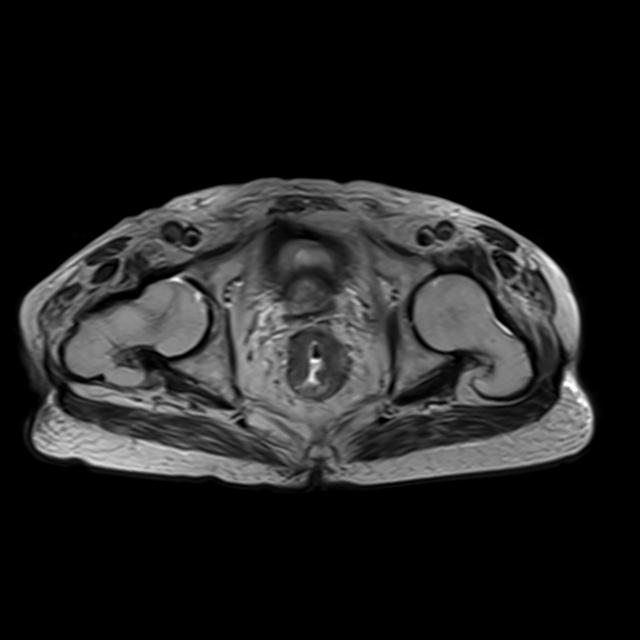

上圖為首發(fā)直腸癌患者,并有睪丸鞘膜積液。